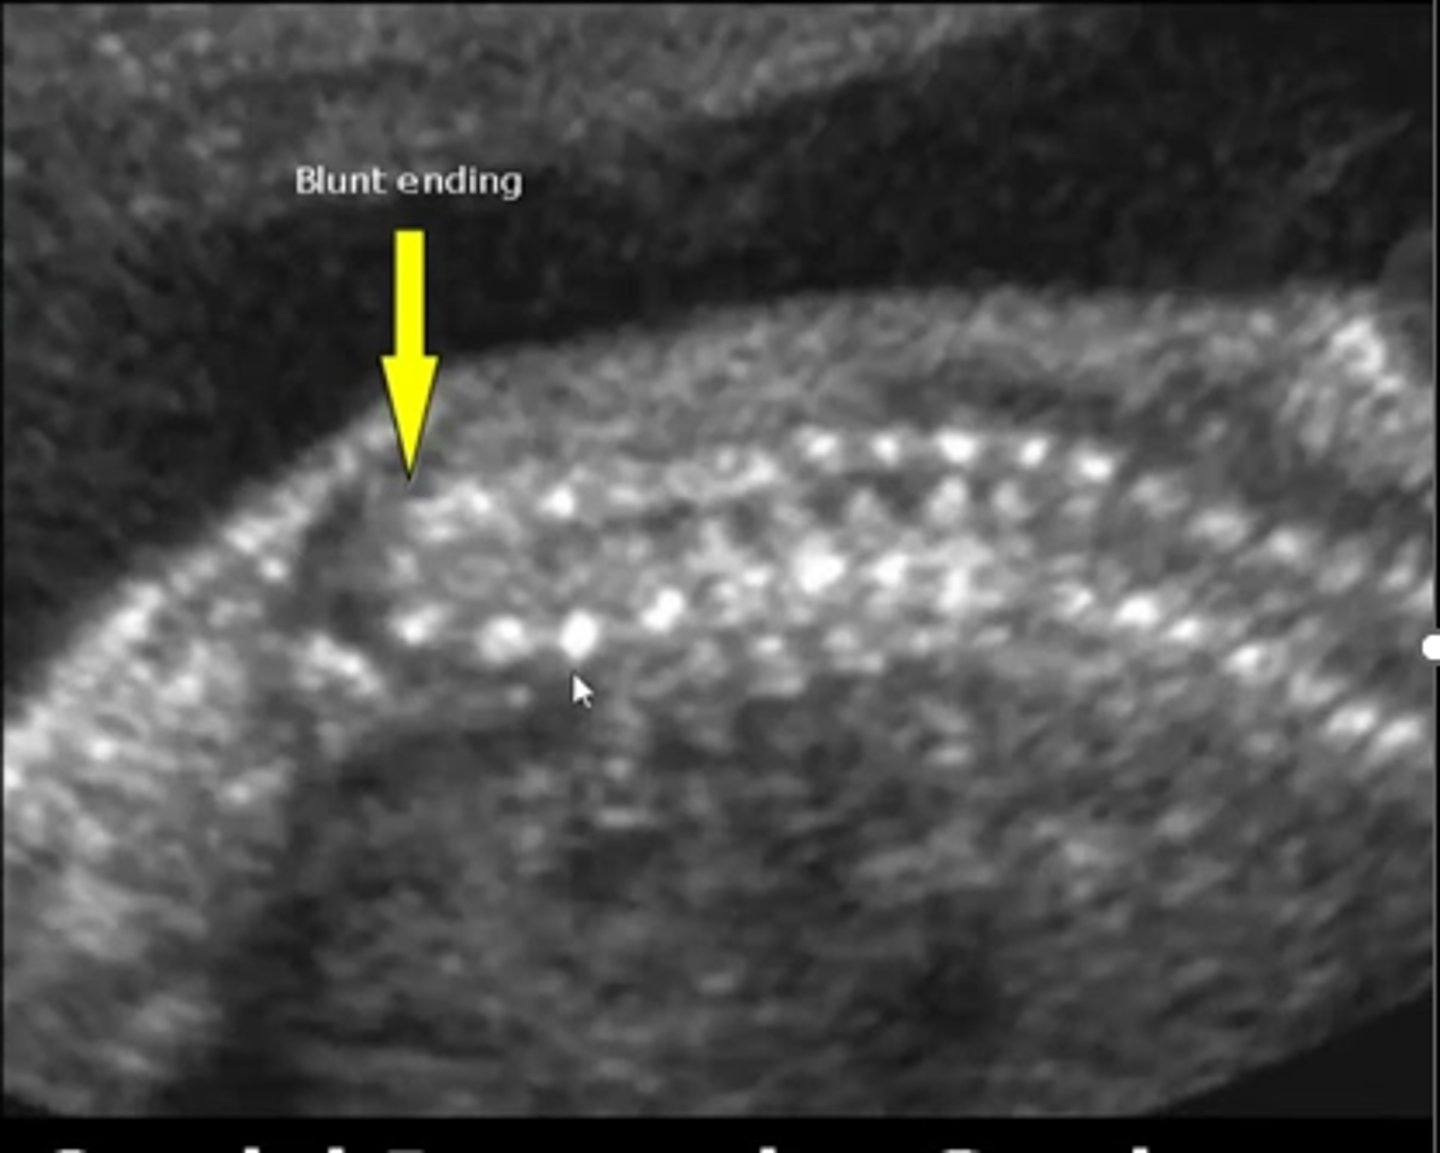

Caudal Regression

Incomplete development of lower half of body

Sacral agenesis

Talipes - cubed feet

Short lower extremities

GU and GI anomalies